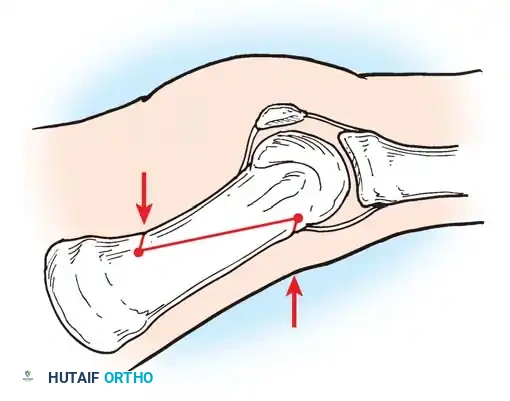

Hallux valgus (lateral deviation of the great toe) is not a single disorder, as the name implies, but a complex deformity of the fi rst ray that frequently is accompanied by deformity and symptoms in the lesser toes (Fig. 78-1). Often the angle between the fi rst and second metatarsals is more than the 8 to 9 degrees usually considered to be the upper limits of normal. The valgus angle of the fi rst metatarsophalangeal joint also is more than the 15 to 20 degrees considered to be the upper limits of normal (Fig. 78-2). If the valgus angle of the fi rst metatarsophalangeal joint exceeds 30 to 35 degrees, pronation of the great toe usually results. With this abnormal rotation, the abductor hallucis, which is normally plantar to the fl exion-extension axis of the fi rst metatarsophalangeal joint, moves further plantarward (Fig. 78-3). In this case, the only restraining medial structure is the medial capsular ligament with its capsulosesamoid portion (inserting into the base of the proximal phalanx) (Fig. 78-4) and capsulophalangeal portion (inserting into the plantar plate). The adductor hallucis, which is unopposed by the abductor hallucis, pulls the great toe further into valgus, stretching the medial capsular ligament (particularly the capsulosesamoid), attenuating this structure, and allowing the metatarsal head to drift medially from the sesamoids. In addition, the fl exor hallucis brevis, fl exor hallucis longus, adductor hallucis, and extensor hallucis longus increase the valgus moment at the metatarsophalangeal joint, further deforming the fi rst ray. The deep transverse intermetatarsal ligament runs between the plantar plates at the metatarsophalangeal joints and does not insert into bone on the adjacent sides of the metatarsal heads. Finally, the sesamoid ridge on the plantar surface of the fi rst metatarsal head (the crista) fl attens because of pressure (abutment) from the tibial sesamoid (Fig. 78-5). With this restraint lost, the fi bular sesamoid displaces partially or completely into the fi rst intermetatarsal space (see Fig. 78-2). In this situation, the patient is bearing less weight on the fi rst ray and more on the lesser metatarsal heads, increasing the likelihood of transfer metatarsalgia, callosities, and stress fracture of a lesser metatarsal.

Two other anatomical variants involving the articular surface of the fi rst metatarsophalangeal joint can lead to hallux valgus. In the fi rst variant, the articular surface of the metatarsal head is offset, resembling a scoop of ice cream sitting at an angle on a cone (Fig. 78-6). This has been described as the distal metatarsal articular angle (see Fig. 78-8). In the second, the articular angle of the base of the proximal phalanx in relation to its longitudinal axis is offset. This has been described as the phalangeal articular angle. Although the normal range of these angles is generally considered to be 7 to 10 degrees for the phalangeal articular angle and 10 to 15 degrees for the distal metatarsal articular angle, exact measurements are diffi cult to reproduce because of the variability of radiographic and measurement techniques. Increasing evidence indicates, however, that the failure to correct these two deformities, especially the distal metatarsal articular angle, can cause unsatisfactory results after surgery in some patients. Forceful straightening of the hallux should be avoided if it sacrifi ces tarsalgia. The entire forefoot must be evaluated for these multiple components of hallux valgus before surgical planning is complete and recommendations can be made to the patient. The controversy continues over which deformity is the essential lesion in hallux valgus: metatarsus primus varus or lateral deviation of the great toe. Each is incriminated as the cause of the other. The strongest data probably support lateral deviation of the great toe as the primary deformity in most patients, followed by medial angulation of the fi rst metatarsal, but metatarsus primus varus may be the principal cause in adolescents. Further controversy surrounds the role of footwear as the prime offender in the development of hallux valgus. Most orthopaedic surgeons have seen unilateral hallux valgus when both feet are clinically and radiographically the same structurally except that one foot has a bunion deformity and the other foot is normal. Evidence supports that hallux valgus may be familial, especially when it occurs in adolescents. Although no study of shod and unshod societies has implicated inappropriate footwear as the sole cause of hallux valgus, after genetic factors, binding, unphysiologically designed footwear probably is the major cause in modern societies. Hypermobility of the fi rst ray also has been suggested as a causative factor in the development of hallux valgus and fi rst metatarsal varus, but this is controversial. Coughlin and Shurnas, Myerson and Badekas, King and Toolan, and Faber et al. offer excellent discussions of this problematic area. Finally, certain anatomical and structural abnormalities almost certainly play a causative role in hallux valgus. Pronated fl atfeet, abnormal insertion of the posterior tibial tendon, increased obliquity of the fi rst metatarsomedialcuneiform joint, an abnormally long fi rst ray, incongruous articular surfaces of the fi rst metatarsophalangeal joint, and excessive valgus tilt of the articular surface of the fi rst metatarsal head and proximal phalangeal articular surface may contribute singly or in combination to the deformity and infl uence the recommended treatment. Hypertrophy of the medial eminence has been described as a component of hallux valgus deformity since the earliest reports; however, more recent investigations, including those of Thordarson and Krewer, have found that bony proliferation is not a component of the pathoanatomy of hallux valgus and that the prominence of the medial eminence results from the combination of metatarsus primus varus and medial deviation that uncovers the articular surface. Thordarson and Krewer compared radiographs of 50 feet in patients who had surgery for hallux valgus deformity with radiographs of 50 feet from a control group without hallux valgus deformity and found little difference in the average width of the medial eminence (4.4 mm and 4.1 mm). With more than 130 operations recommended for the treatment of hallux valgus, it is practical to describe only